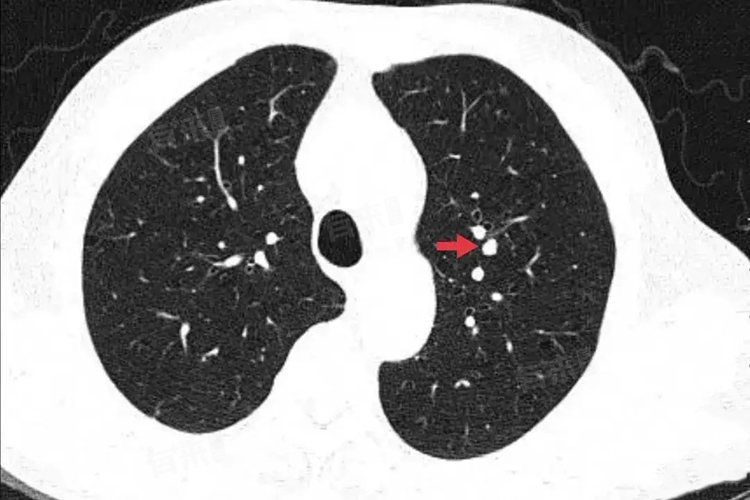

- 肺癌是导致肺部小结节的严重病因,尤其是在长期吸烟、有肺癌家族史等高危人群中。早期肺癌如原位腺癌、微浸润腺癌,可能仅表现为右下肺的小结节。这些小结节在影像学上可能具有恶性特征,如分叶征、毛刺征、胸膜牵拉征等。

分叶征指结节边缘呈凹凸不平的多个弧形,形似花瓣;毛刺征表现为结节边缘向周围伸展的细短毛刺;胸膜牵拉征则是结节与胸膜之间存在条索状影相连,这些特征提示结节的生长方式具有侵袭性,需高度警惕。